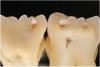

Fig 7. ICDAS code 0: Sectioned tooth confirms stain not indicative of carious penetration of fissure.

Figure 7